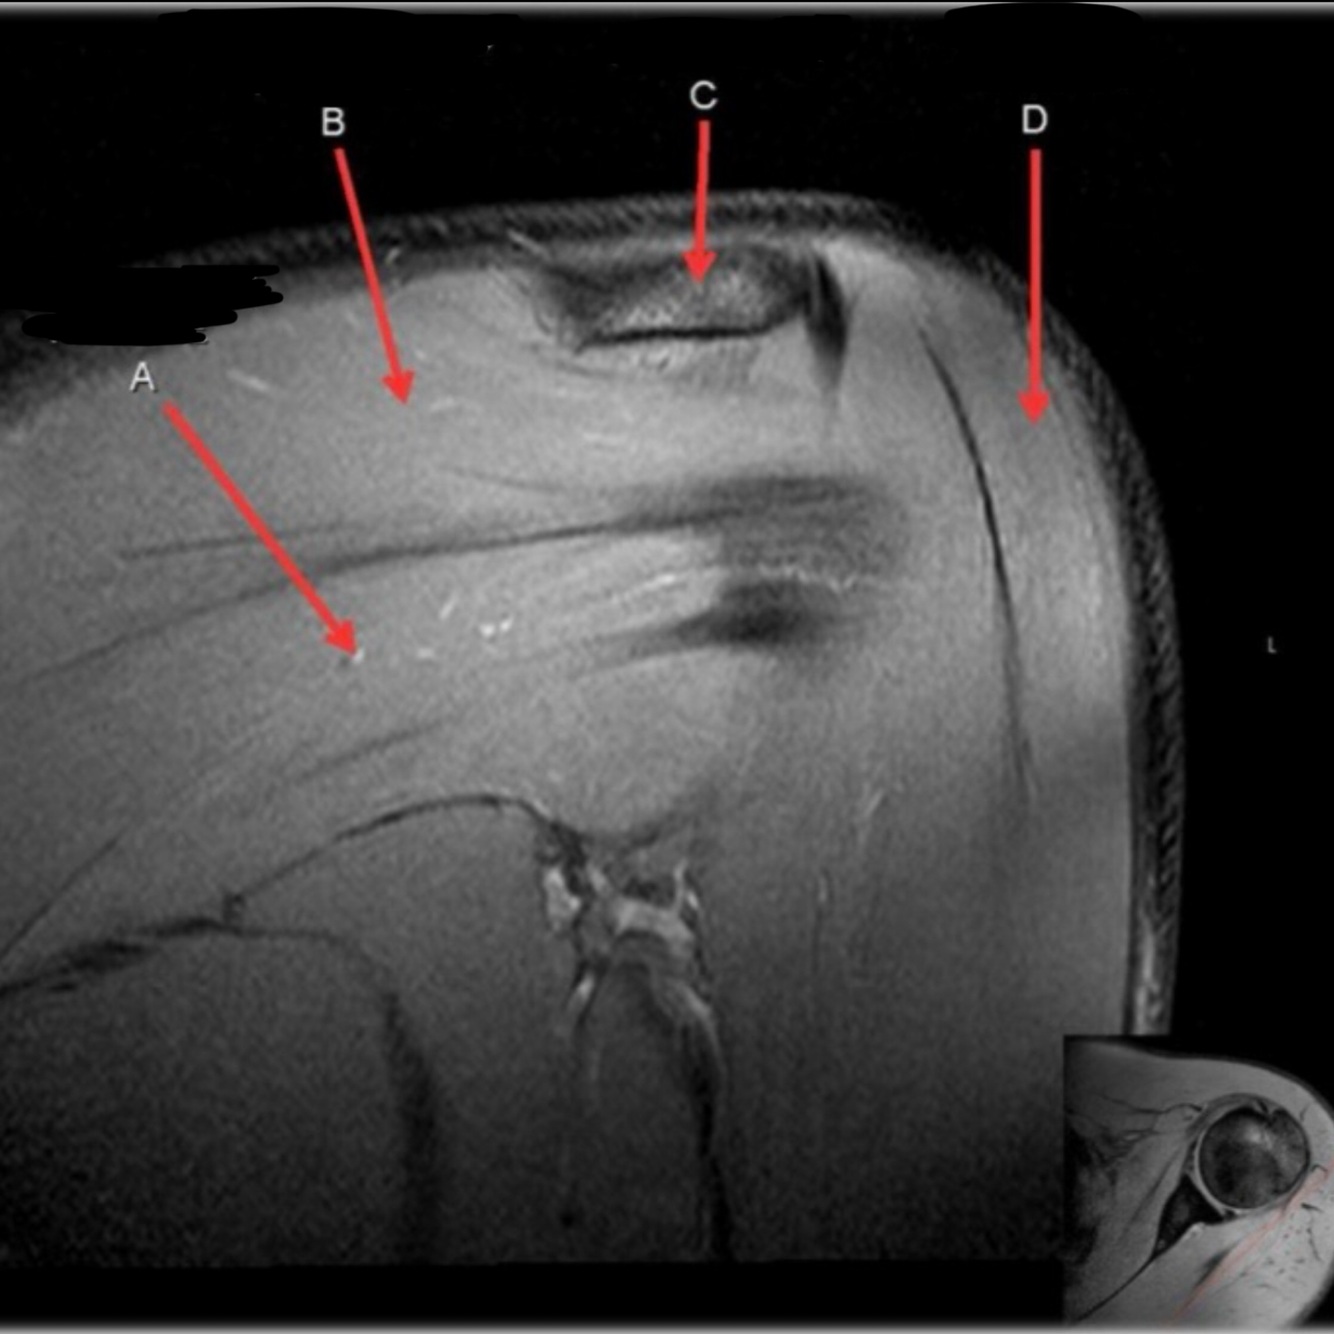

Q

What is letter A?

What is letter B?

A

ACROMION

5

What is letter C?

6

What is letter D?